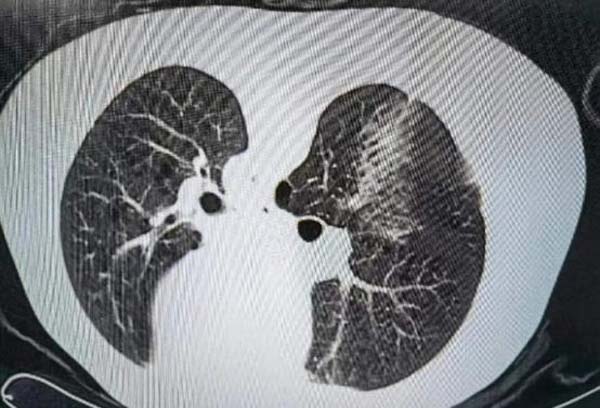

穿刺活检后:

消融治疗中: